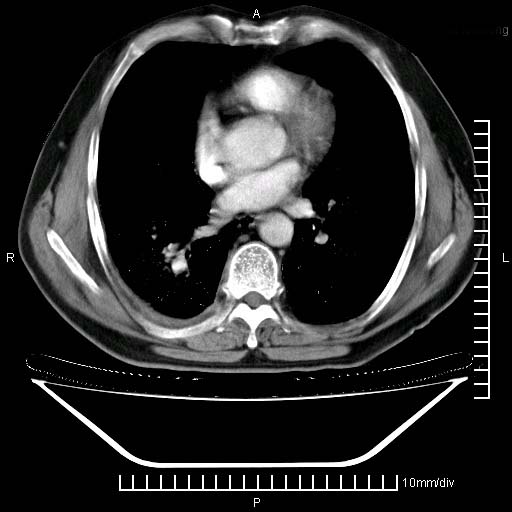

标题: CT24043:胸部增强:男性,60岁

既往肺结核,近10几天,咳嗽,咳痰,右侧胸痛,疼痛较明显,右上肺斑块考虑结核灶胸膜粘连,增强,可惜动脉期没有定好,未见强化,可延迟4分后又见较明显强化,中心见低密度影,如果说结核是边缘强化,可这个灶强化的面积挺大的,让人很挠头。

延迟4分后

[img][/img]